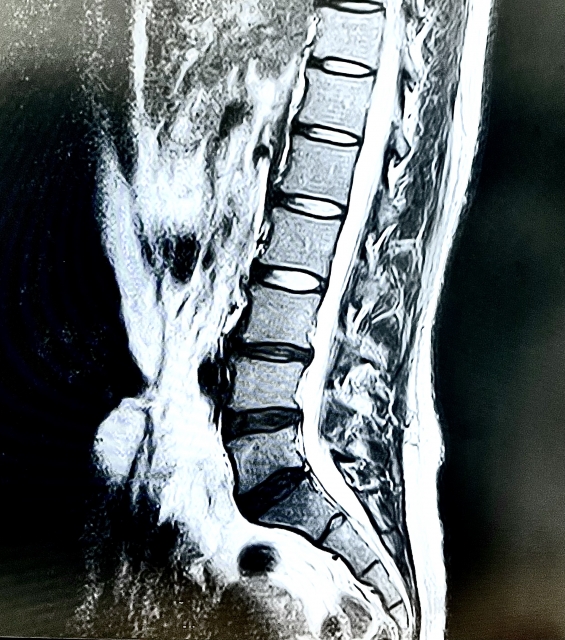

特異的腰痛とは、レントゲンやMRIなどの検査で原因が特定できるもの(腰椎椎間板ヘルニア、脊柱管狭窄症、腰椎すべり症など)

画像に写ったものが腰痛の原因とは限らない

さらに、やっかいなことに、レントゲンやMRIなど検査で、画像にヘルニア、脊柱管の狭窄、腰椎のすべりが写ったかといって、それが本当の原因とも言えないんです。

ヘルニアには、無症候性ヘルニアというものがあります。

腰痛の症状がない人でも、MRIを撮影すると60歳未満で20%、60歳以上だと40%の方にヘルニアが見つかるというデータもあります。

脊柱管の狭窄や腰椎のすべりなどは、老化やけがによっておこることが多いので、外科手術によって広げたりつなぎ合わせたりしなければ、大きく状態が変わることはありません。

ですが、腰椎ヘルニア、脊柱管狭窄症、腰椎すべり症の症状は、整体で改善します。

整体で症状が改善した方が、もう一度レントゲンやMRIを撮ると、そこには脊柱管の狭窄や腰椎のすべりは写ります。

画像に写っているのが原因であれば、その原因が画像上変化していなければ症状は変わらないはず。だけど、症状は変わる。

ということは、画像に写るものが全て実際の症状の原因ではないということです。

もちろん、画像と症状が一致することもありますが、その割合は少ないといわれています。

画像には今までの結果が写っている

当院は、レントゲンやMRIには、今までその場所にどのような負担がかかってきたのかという結果が写っていると考えます。

ヘルニア、脊柱管狭窄、椎間板がつぶれるなど、画像に写る変化は、短期間でおこるものではなく長期間に渡って負担がかかることによりおこります。

ヘルニア、脊柱管狭窄、椎間板がつぶれているなどが画像に写った方は、腰により多くの負担が掛かってきたわけだから改善まで時間を要するかもしれないなと一つの参考にします。